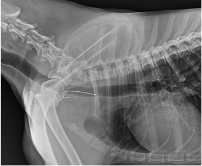

Orthopaedic surgery encompasses any surgery that is related to bones or joints. It includes procedures such as fracture repairs, ligament repairs and spinal surgery, to name a few. Our veterinarians’ high level of expertise and our practice’s fully equipped surgical suite allows us to perform certain orthopaedic surgical procedures that your pet may require.

- Fracture (broken bone) repair